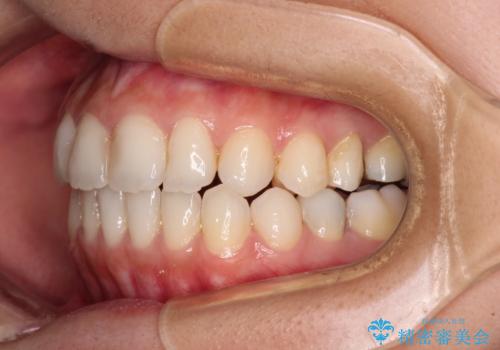

- オープンバイトのため、話しているときの見た目が気になるとのことで来院された患者様です。

下顎骨は左側にシフトしており、咬み合ったときには奥歯と前歯の一部しか接触していない状態でした。

骨格的な左右差は歯列矯正は改善できないため、上下歯列が全体的に接触することをゴールとしてインビザラインにて矯正治療を行うこととしました。

前歯のデコボコの解消と並行して上下の奥歯を圧下させるようにすることで、前歯を接触させるように計画しました。

上下の隙間に舌が入り込むことがオープンバイトの原因であったため、舌の筋肉のトレーニングも並行して行い、後戻りの抑制を図りました。